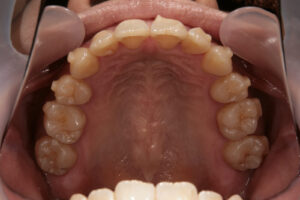

インビザラインで失敗した38歳女性

Invisalign failure - Gum recession1

Invisalign failure – Gum recession1

歯肉が退縮している

Invisalign failure - Gum recession

Invisalign failure – Gum recession

全体的な汚れが目立つ